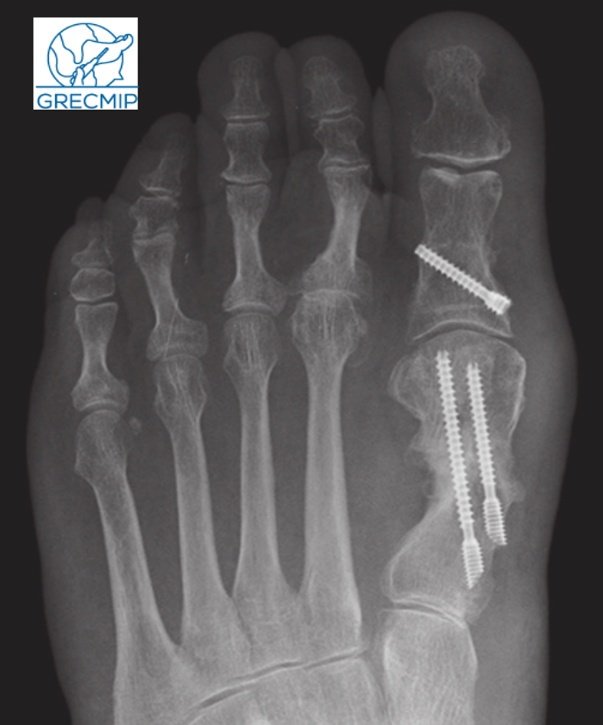

Рентген после операции Hallux valgus